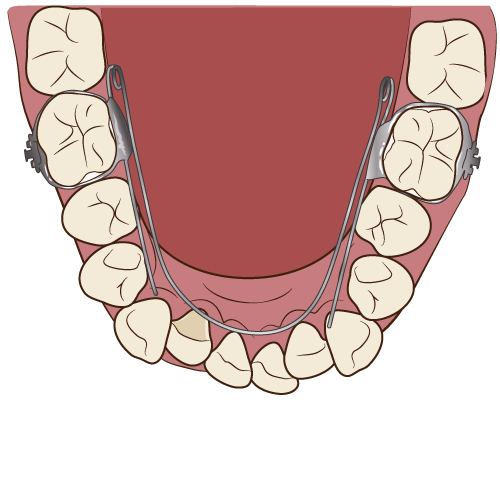

・クワッドヘリックス(顎の拡大装置)

・舌側弧線装置